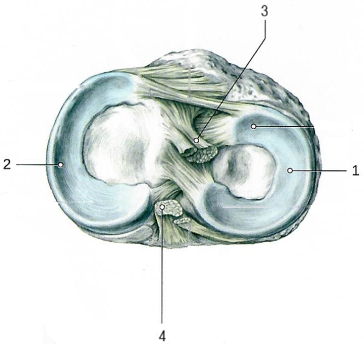

Коленный сустав по строению сложный, комплексный, по форме мыщелковый, по функции двуосный.

Сустав образован мыщелками и надколенниковой поверхностью бедра, верхней поверхностью большеберцовой кости, суставной поверхностью надколенника (имеет медиальный[2] и латеральный[1] мениски).

В суставе возможны сгибание и разгибание голени, вращение (при полусогнутом положении голени).

Связки, укрепляющие коленный сустав.